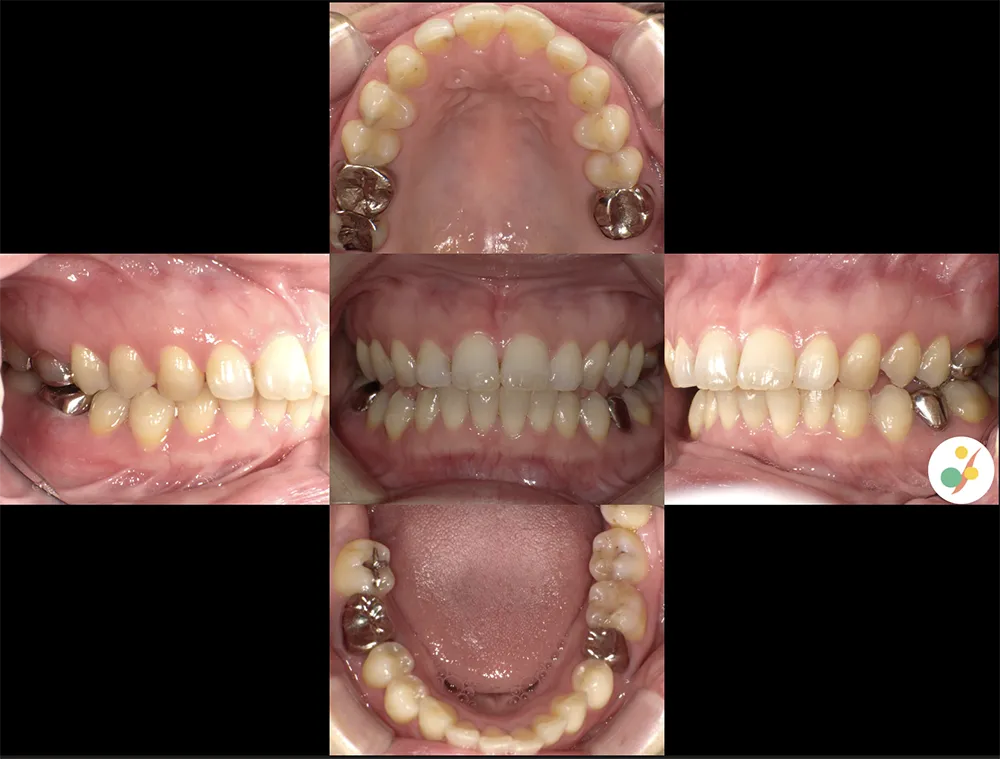

視覚資料として提出する検査結果の一例

口腔内写真